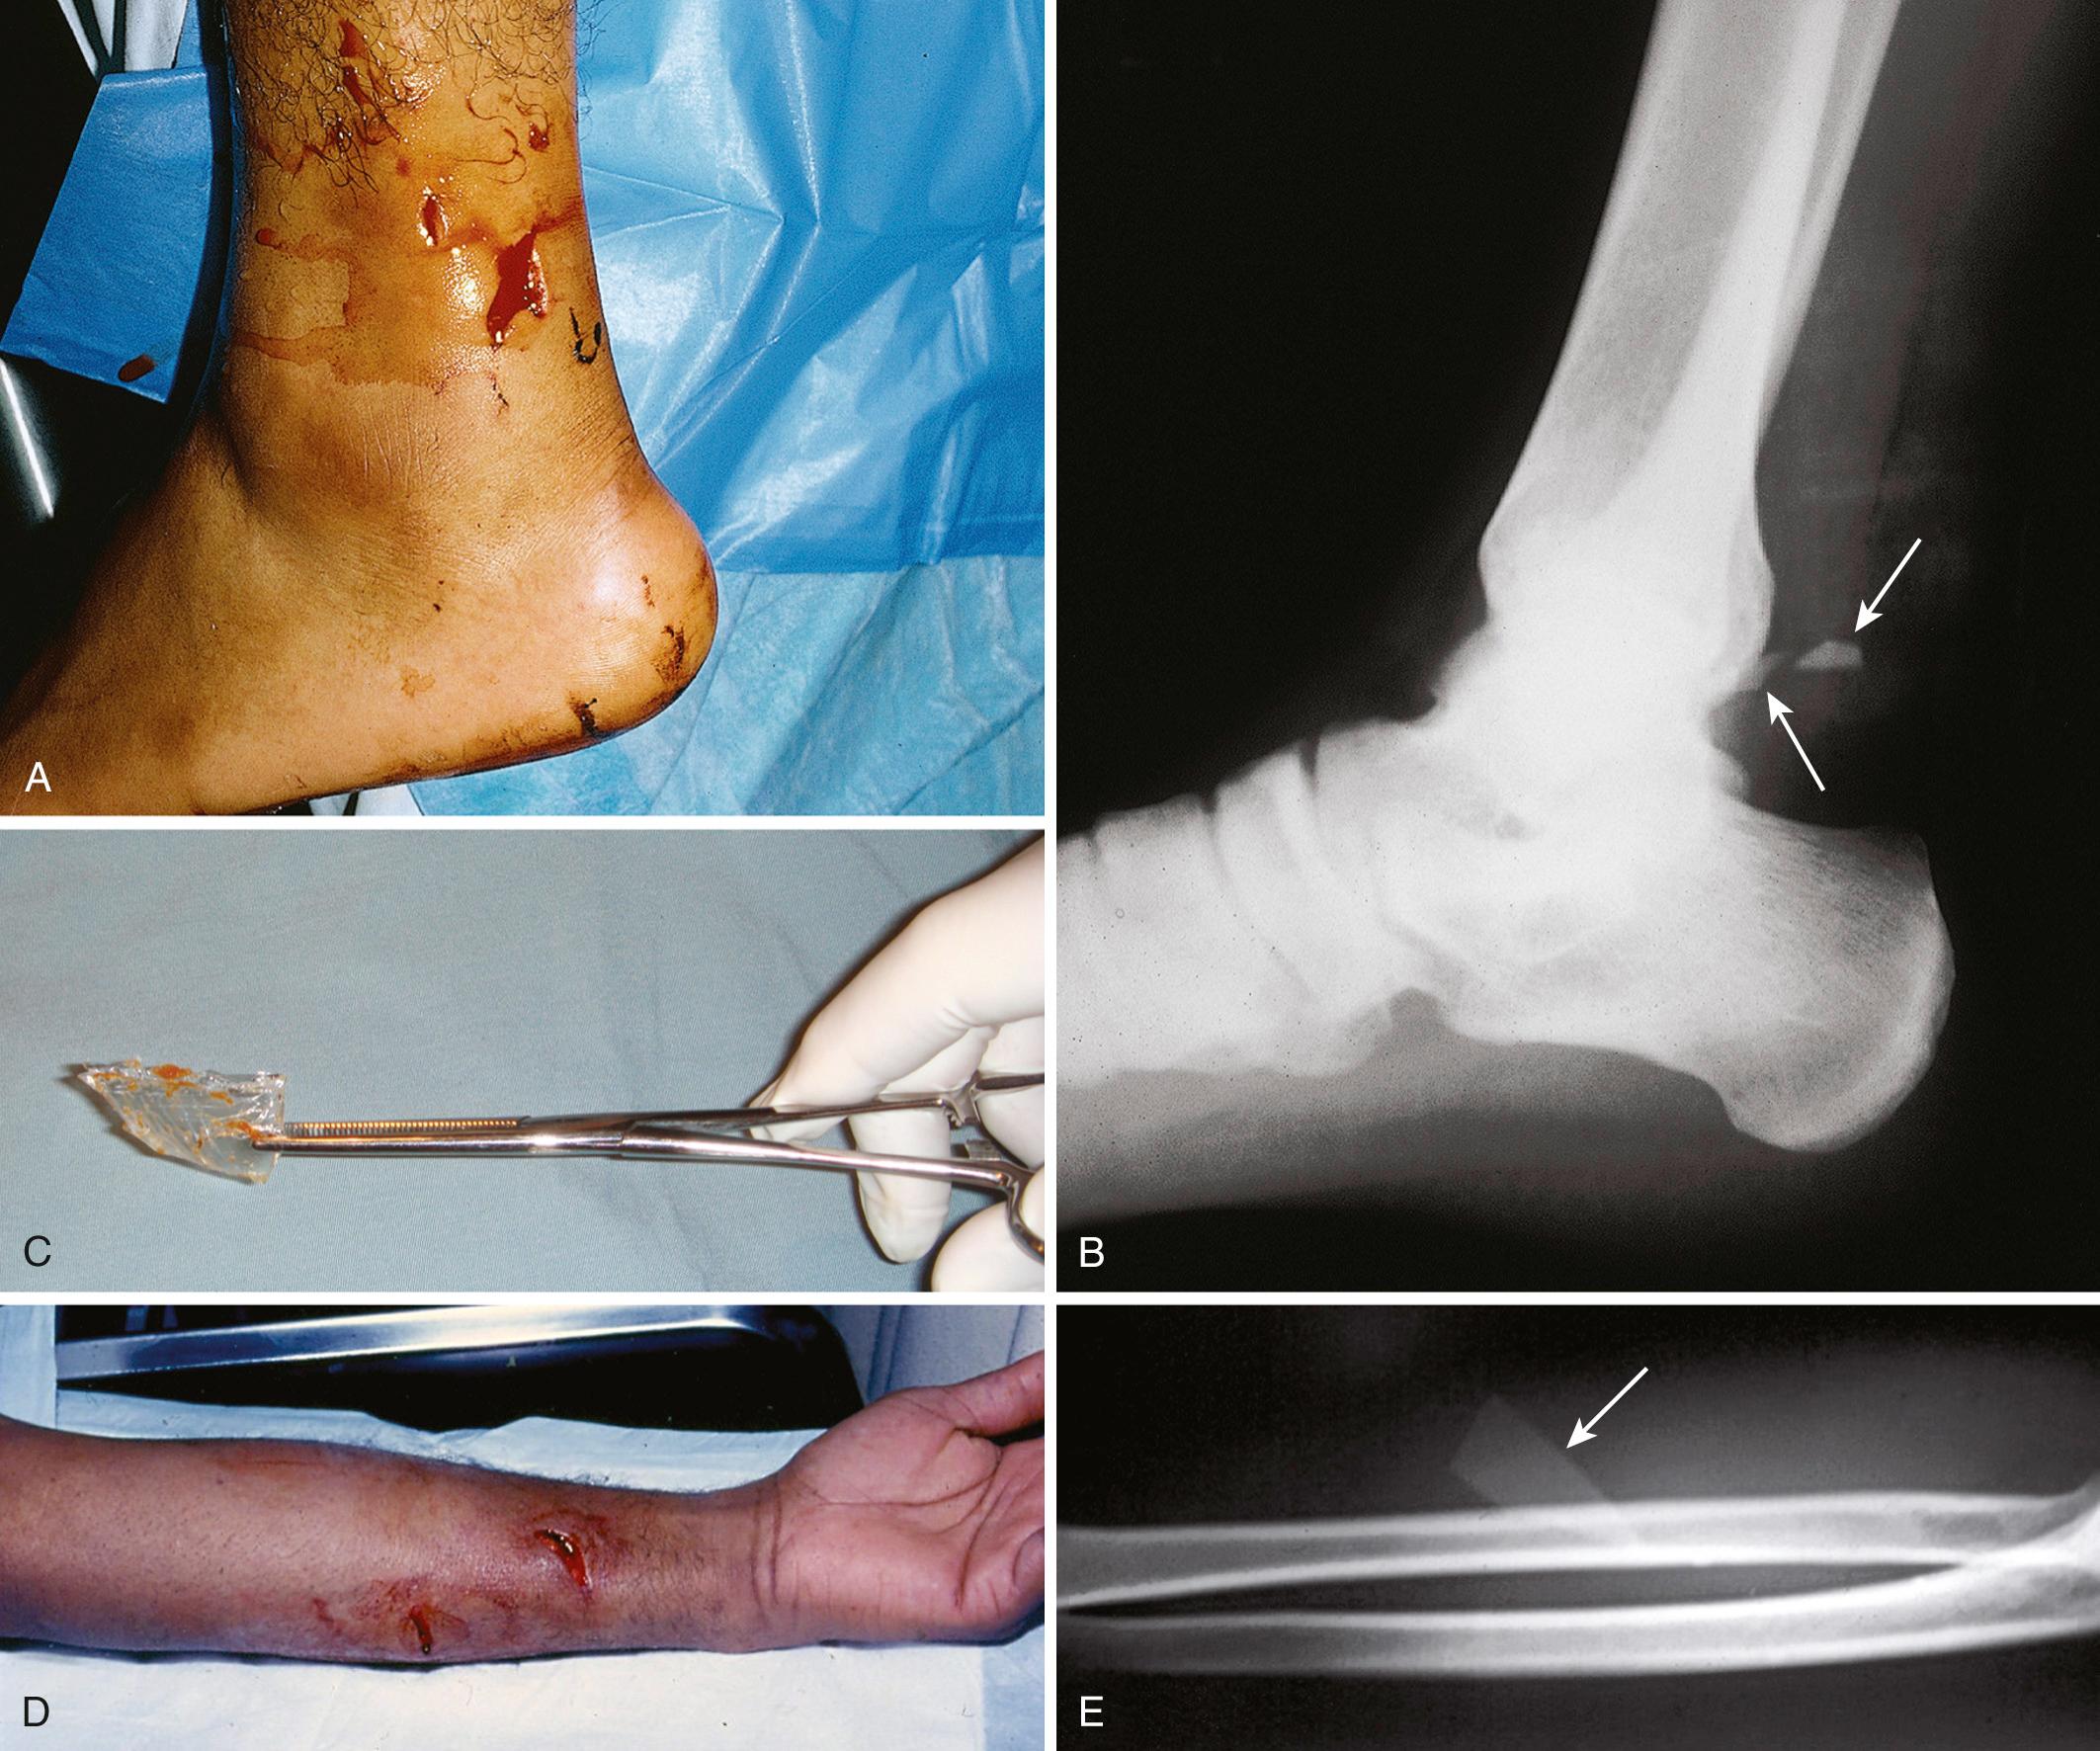

A foreign body (FB) is any substance that is not naturally part of the body. These cases are common in the clinical setting. An FB should be suspected whenever the skin is broken. A thorough history and physical examination are essential to assess the risk for an FB. During assessment, FBs may not be obvious especially when the wound may appear closed, but they should be considered whenever the history is particularly concerning. For example, a patient with an apparent “sprained foot” who was walking without shoes and experienced a sharp, sudden pain in the foot may have a needle, toothpick, or any other similar type of FB ( Fig. 36.1 ). Certain mechanisms of injury, such as punching or kicking out a window or stepping on an unknown object while walking in a field or stream, are often associated with a retained FB. Mechanisms that make FBs less likely include lacerations from metal objects; however, if considerable force was applied during the injury and the object is not available for inspection, radiographic imaging may be warranted because bone may have been encountered and a small section might have splintered off the offending object. The history should also include whether the patient perceives or suspects an FB. Steele and associates found that the negative predictive value of patient perception was 89% but that the positive predictive value was just 31%. Importantly, the patient's past medical history should be explored for allergies to local anesthetics, bleeding diatheses, diabetes mellitus, vascular disease, uremia, immunocompromised state, or other diseases that would affect wound healing or management.

Figure 36.1, A, A common foreign body (FB) in the foot is a splinter, toothpick, pin, or needle that is impaled while walking barefoot on a carpet. This sewing needle (arrow) was obvious, but in the absence of a history of an FB, some FBs may be mistaken for a simple puncture wound, heel spur, stress fracture, contusion, or tendinitis. B, Postoperative radiographs demonstrate complete removal. C, This patient fell, landed on a metal pipe, and suffered a deep laceration in the thigh. A radiograph was taken to rule out a fracture, and the key was seen but thought to be an artifact (i.e., an item left on the backboard). During the examination, the key was found embedded in the wound. It had been in the patient's pants pocket and was forced into the wound by the pipe during the injury.